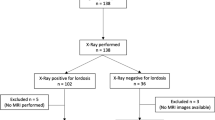

Deidentified udMRIs of 50 adults, referred for reasons other than CCI, were captured at three positions (maximal flexion, maximal extension and neutral). Images were analyzed, providing measures of basion-axial interval, basion-axial angle, basion-dens interval (BDI) and the Grabb–Oakes line (GOL) for all three positions (12 measures per participant). All measures were independently recorded by a radiologist and neurosurgeon to determine their reliability. Descriptive statistics, correlations, paired and independent t-tests were used. Mean (± 2 SD) identified the reference range for all four measures at each craniocervical position.

Staff of a medical diagnostic imaging center (Western Imaging Group, NSW, Australia) provided deidentified, udMRI images of the craniocervical region of male and female patients 18 years or over. The MRI used in this study was the FONAR UPRIGHT® Multi-Position™ MRI (0.6 Tesla). All were referred for reasons other than CCI. Images of patients who were referred with head or neck trauma, whiplash associated disorder, rheumatological conditions of the craniocervical spine or a hereditary disorder of connective tissue (including but not limited to Ehlers-Danlos Syndrome, Marfan or Loeys-Dietz Syndromes or Osteogenesis Imperfecta) were excluded from the study.

We aimed to utilize 50 participants’ udMRI for this exploratory study, similar sample size to other investigative MRI studies related to craniocervical measures [7, 20]. To determine the inter-tester reliability of the four measures used in the protocol, two of the investigators (senior radiologist ML and senior neurosurgeon PJR) independently measured these on all three images (neutral and maximal flexion and extension). The diagnostic imaging center provided demographic data only to the chief investigator (LLN) to ensure that those performing the measures were blinded to each patient’s age, sex and reason for referral. A priori, we chose to determine the inter-tester reliability (ICCs) of all four measures in each of the three craniocervical positions for the first 20 participants. If any of the twelve ICCs were not acceptable (< 0.7), the assessors would meet to refine the protocol and remeasure the scans and ICCs would be recalculated. If the inter-rater reliability was deemed acceptable, the measures of the radiologist would be used for the remainder of the analysis as this would be consistent with clinical practice.

The maximal craniocervical flexion and extension images together with the neutral image in the median sagittal plane of 50 participants were extracted from the series of images captured using udMRI. The mean age (SD, range) of these participants was 41.2 years (± 9.7, 24–69) with no significant age difference between sexes (41.2 years (± 9.3, 24–58) for females; 41.3 years (± 10.3, 27–69) for males (p = 0.98)). Fifty percent of the cohort were male. All data were normally distributed. The reasons for referral for udMRI were as follows: 72% cervical radiculopathy, 24% neck pain and 4% cervical myelopathy.